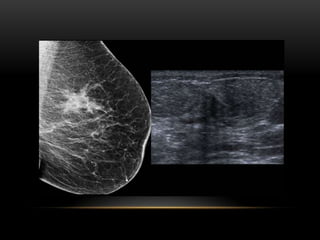

ULTRASONIDO

• Mamas densas

• Caracterización de nódulo palpable mastográficamente no

visible

• Caracterización de nódulo mastográficamente visible

• Caracterización de asimetría focal

• Aplicación de Doppler

• Biopsia

PATRÓN DEL TEJIDO GLANDULAR

ECOGRÁFICO:

1. Ecoestructura homogénea grasa

2. Ecoestructura homogénea

fibroglandular

3. Ecoestructura heterogénea